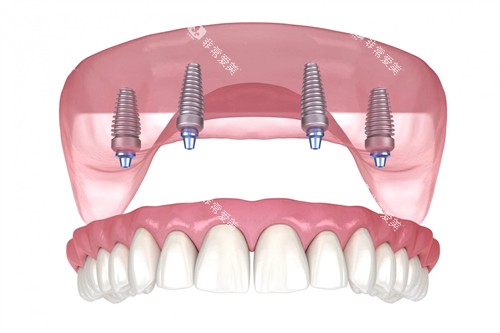

前牙区种植建议选择全瓷冠提升美观度,后牙区可优先考虑性价比更高的烤瓷冠。缺牙数量较多者采用All-on-4半口种植方案,较传统种植节省30%-40%费用。